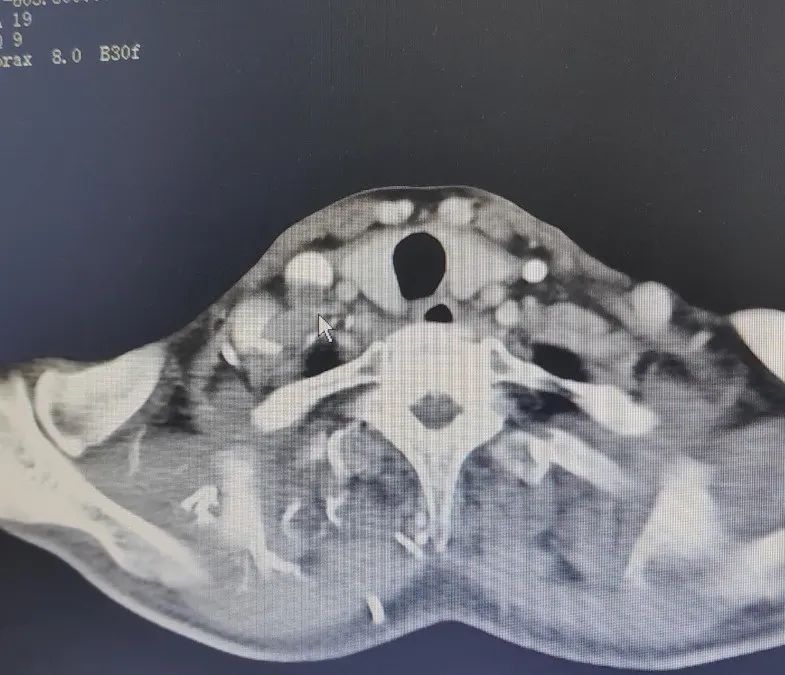

在醫(yī)生的建議下,老張接受了化療聯(lián)合免疫治療的方案,期間還進行了33次放療。一開始,老張的復查結(jié)果還是可喜的:右咽隱窩腫瘤原發(fā)灶基本消失,聲嘶、咽喉異物感的癥狀好轉(zhuǎn)。但2023年10月,老張的右側(cè)鎖骨上淋巴結(jié)腫大,左氣管食管溝也多發(fā)淋巴結(jié),活檢結(jié)果提示:轉(zhuǎn)移可能性大。

2023年11月

碘粒子植入術(shù)前

影像檢查

2024年6月

碘粒子植入術(shù)后

7個月復查結(jié)果